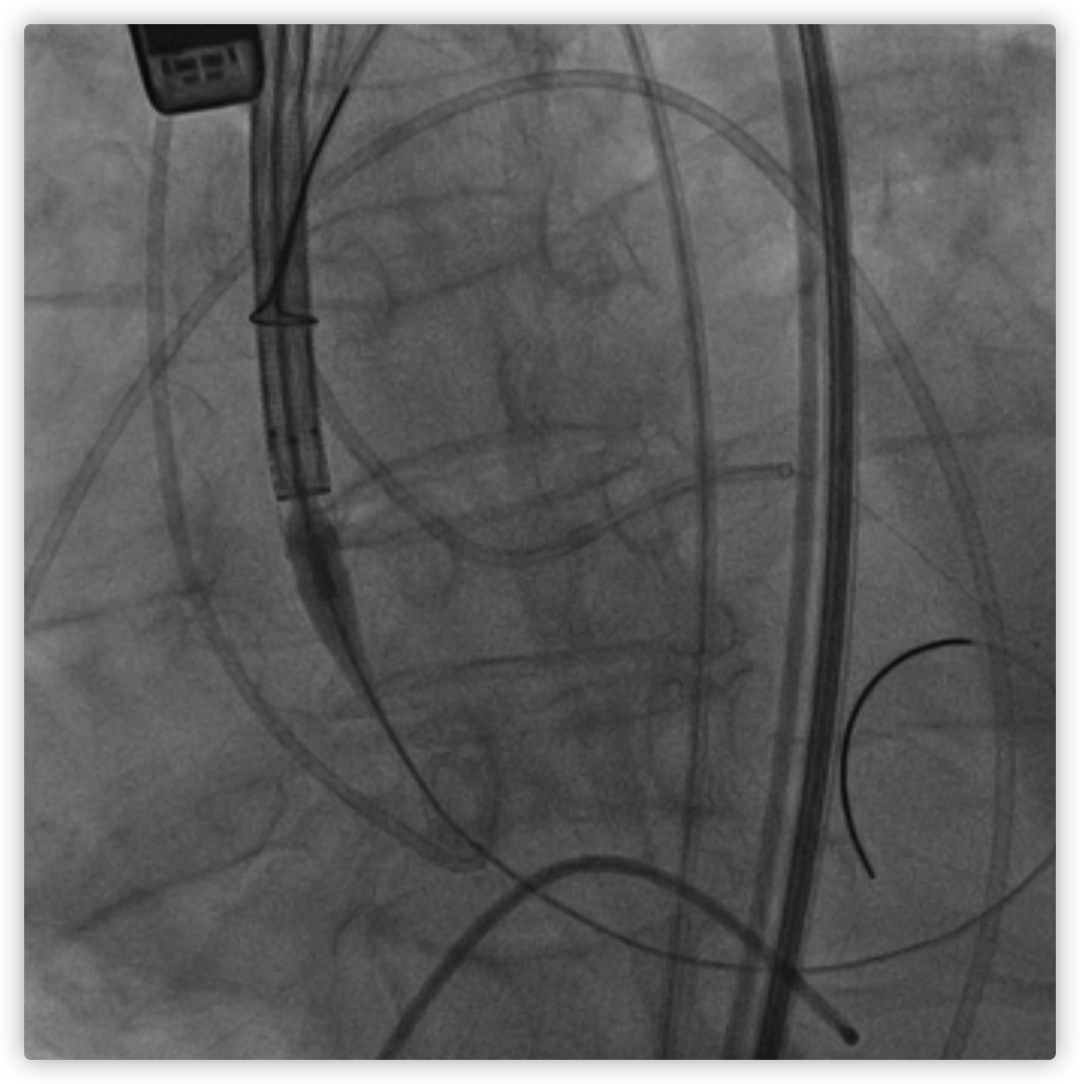

26VenusAplus+snare

瓣膜内22mm球囊后扩张,左冠无显影